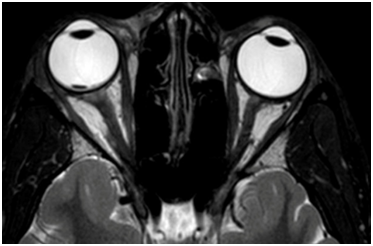

A 15-year-old healthy male presented with an ocular injury sustained while playing basketball. He described a finger poke incident with the contact made with the lower aspect of his right eye. Immediately following the injury, he described loss of vision of the right eye. On presentation to the emergency eye clinic 2 hours later, his visual acuity was no light perception in the right eye. A right relative afferent pupillary defect was present. A conjunctival tear and associated chemosis was present in the inferior bulbar conjunctiva. A micro-hyphaema with 2+ red cells was found in the anterior chamber but the cornea, lens and intraocular pressure were all normal. Examination of the posterior segment revealed localized vitreous haemorrhage arising from the disc. The disc itself appeared disorganized and recessed behind the globe with an obvious defect in the disc superiorly (Figure 1). Gentle palpation of the globe during fundus examination showed that some streaks of vitreous haemorrhage adjacent to the disc were mobile and could pass through the disc defect with gentle palpation and return into view on release of palpation. There was retinal pallor affecting the superior temporal and nasal aspects of the retina (Figure 2). A B-Scan ultrasound demonstrated alteration in the normal contour of the optic nerve/ globe junction and hypo echogenic area adjacent to the nerve (Figure 3). MRI of the brain and orbit showed disruption in the area of lamina cribrosa of the right eye (Figure 4). At 3 weeks following the injury, progressive dense vitreous haemorrhage prevented visualization of the posterior pole (Figure 5). Subsequent follow up after one month showed that the vitreous haemorhage disperse spontaneously, with persistent optic nerve disorganization and no improvement in vision.

Figure 4 Axial T2 weighted MRI image of orbit demonstrating widened and altered nerve globe junction.